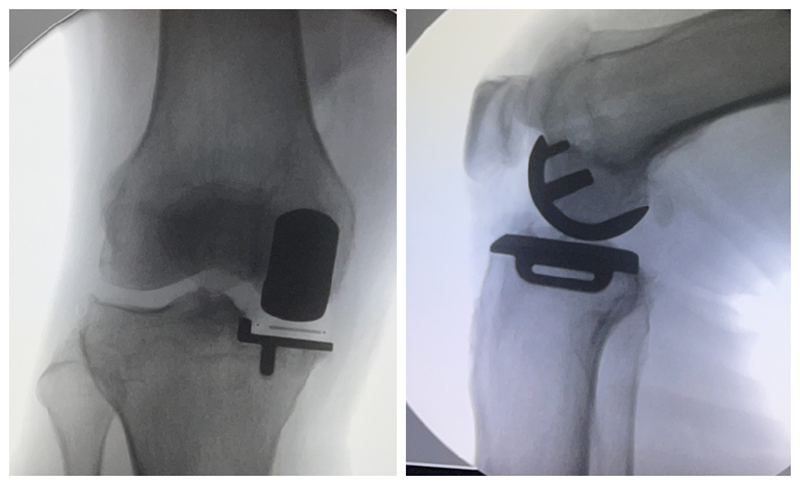

内侧单髁置换术(非骨水泥型)

术前

术后检查

膝关节单髁置换术后的翻修率的一个主要原因是无菌性假体松动。临床上常常用术后X线平片上是否出现透亮带来判定假体是否松动。事实上部分骨水泥型单髁假体,术后x线片常常可见生理性透亮带,容易误诊为假体松动,从而导致不必要的术后翻修,生物型单髁置换假体的推广减少了单髁翻修率,延长了假体的使用寿命。

现阶段生物型单髁假体也逐步被越来越多医生与患者选择。对于生物型假体,需要注意以下几点:(1)垂直截骨开槽避免用常规骨水泥型假体工具,以免开槽过宽导致假体置入松动。(2)开槽过程中需要特别谨慎小心,敲击力度适宜,以防胫骨劈裂骨折。(3)年龄大,骨质疏松明显以及股骨髁坏死病例用生物型假体应更加慎重。